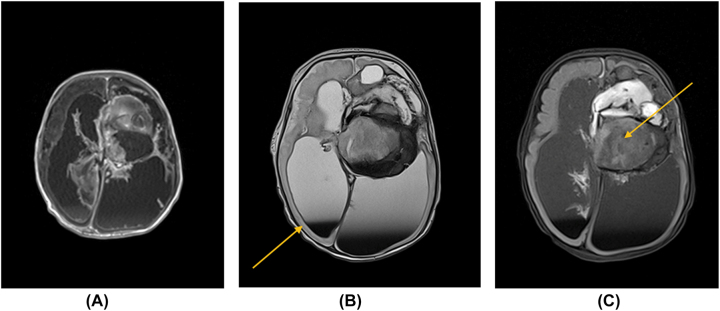

Case presentation: In the 29th week of pregnancy, a female fetus was diagnosed with intracranial hemorrhage complicated by hydrocephalus. Postnatal brain MRI imaging showed a solid proliferative lesion of the left hemisphere with dilatation of the ventricular system. Brown cerebrospinal fluid was collected during the puncture of the left lateral ventricle to reduce hydrocephalus. No tumor cells were detected by cytology. Due to increasing hydrocephalus, the patient was qualified for Rickham reservoir implantation. On day 27th, a craniotomy was performed to determine the etiology of recurrent prenatal intraventricular bleeding. During surgery, the bleeding mass raised the suspicion of neoplasm-histopathological examination of the retrieved tissue diagnosed WHO stage IV malignant glioma. The patient died at 8 months of age.

Abstract Image